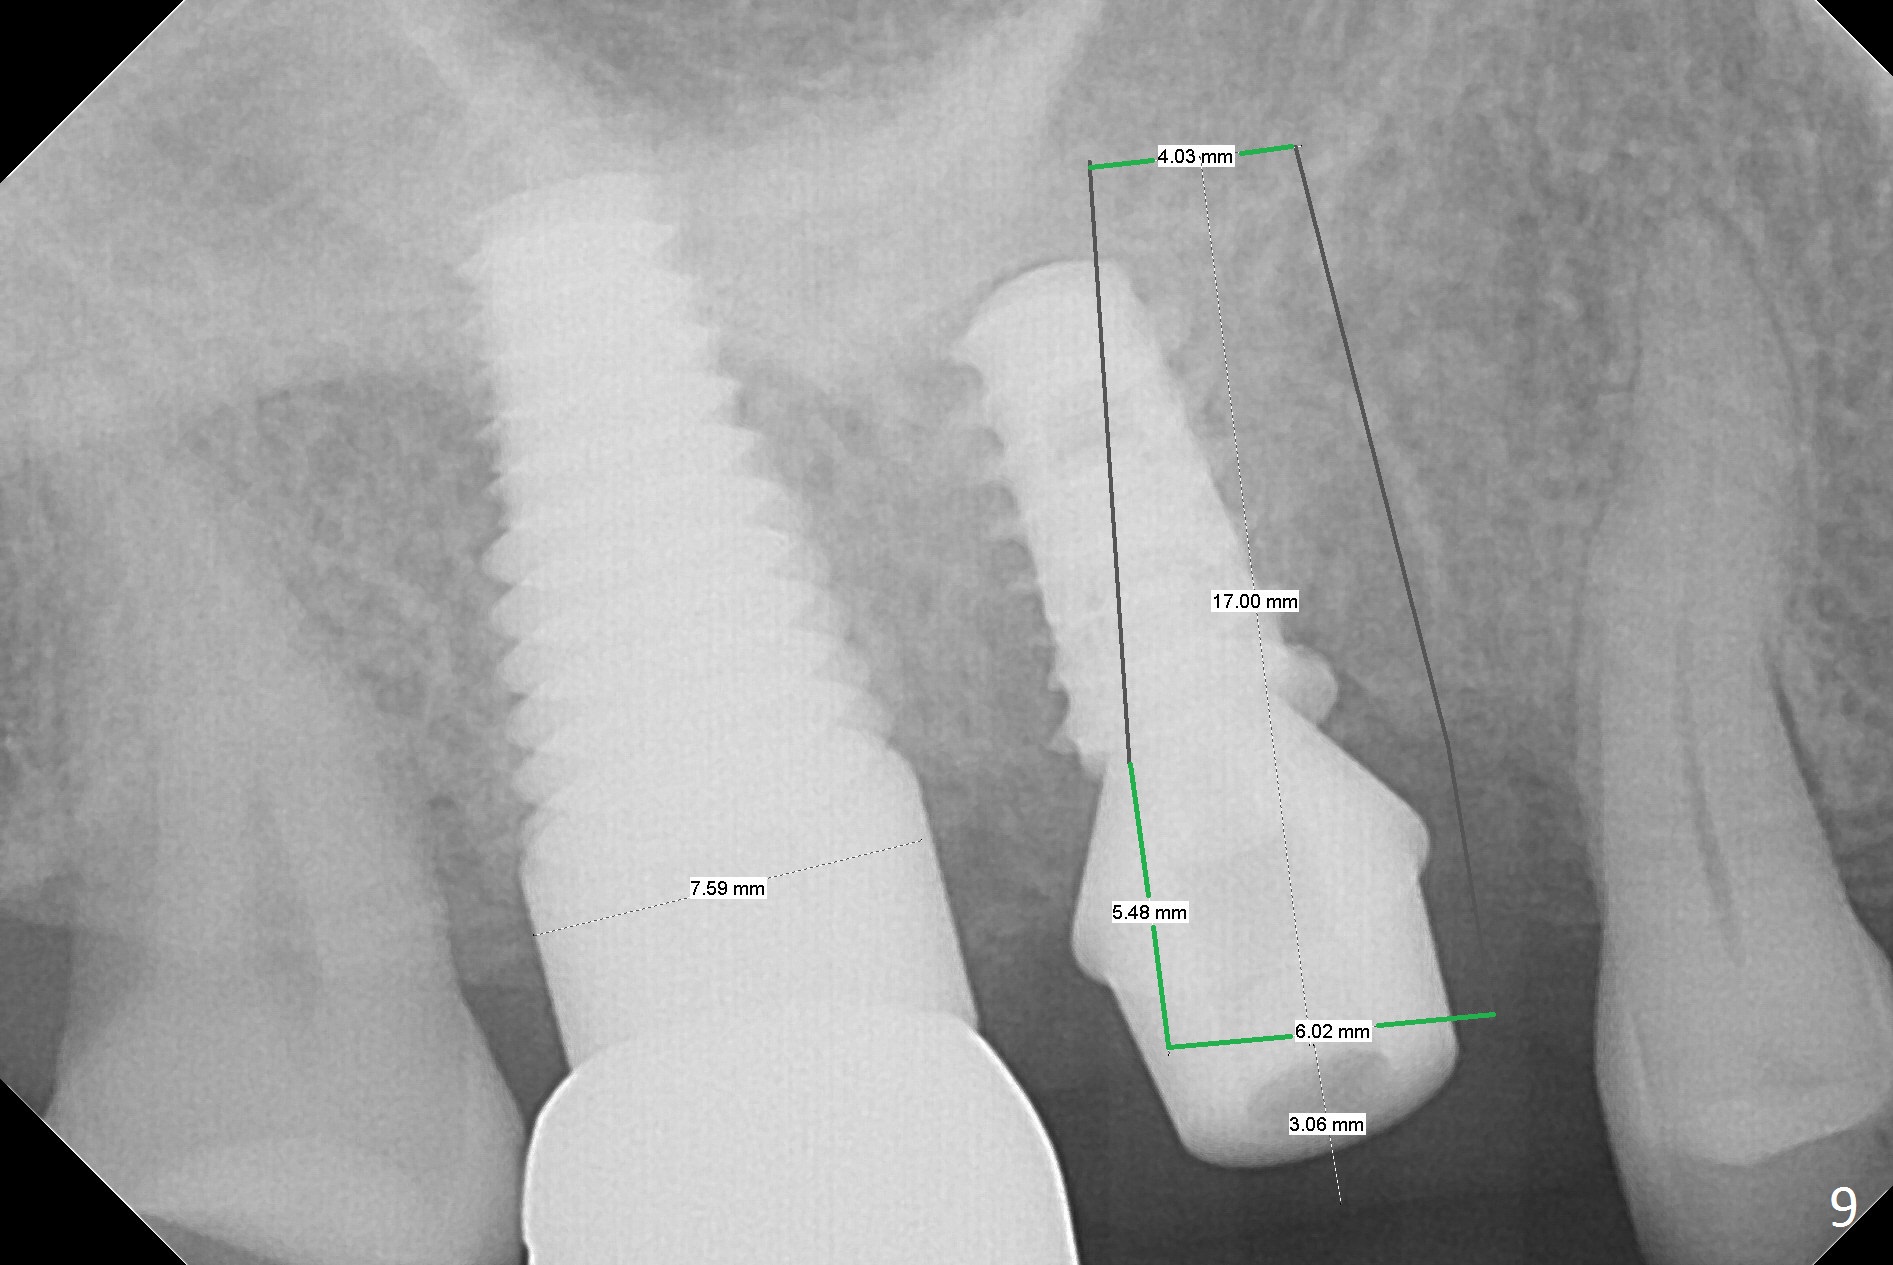

The patient returns with chief complaint of crown is loose with pain 3 months postop (Fig.7). Under local anesthesia, the provisional is removed. The gingiva is erythematous. The implant has mobility. A healing abutment is placed (6x2 mm). One month later, the implant remains unstable. The patient is scheduled to return 3.5 months postop to either retighten the implant with healing screw or replace with a 6x17 mm Tatum implant (Fig.9) after changing trajectory (Fig.8 red arrow).